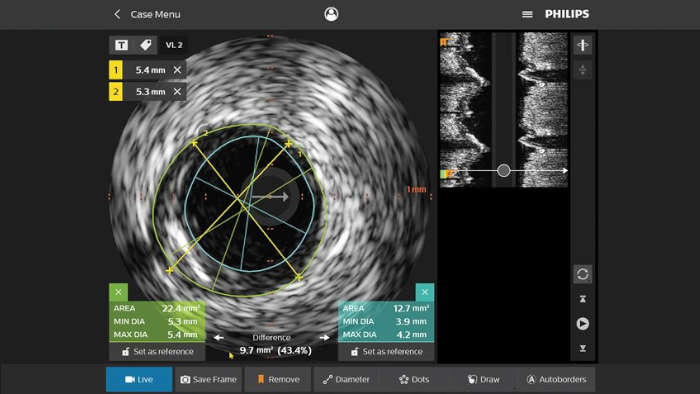

フィリップスの冠動脈イメージングカテーテルは、疾患の位置や、石灰化および血栓などの病変形態の特定に役立ちます。IVUSを活用して、ステントのサイズ決めや、治療結果の確認ができます。